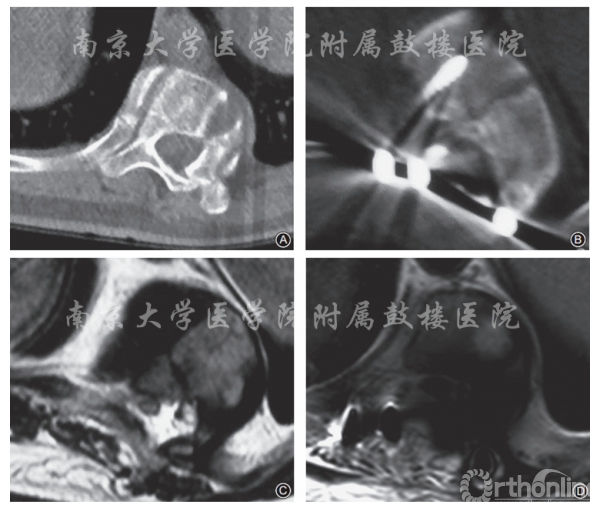

本组手术时间5〜7.2h,平均5.8h;术中出血600〜2300ml,平均1150ml。术前MRI图像显示12例患者侧后凸顶椎凹侧脊髓均受压变形,术中可见行脊髓内移术后硬膜囊较术前明显增粗,探查脊髓受压程度较术前明显减轻,提示脊髓向凹侧移位。术后CT示顶椎区凹侧椎板、椎弓根、肋骨头及横突缺如,MRI示脊髓压迫解除(图3)。12例患者随访1~5年,平均2年。

图3 男,16岁,术前诊断为先天性脊柱侧后凸畸形(T10、T11半椎体)伴不全瘫;术前检查双下肢肌力减弱、感觉减退、行走不稳,双下肢跟腱、膝腱反射亢进,Babinski征阳性,Frankel分级C级;行脊髓内移术+后路矫形内固定术(T5~L3) A 术前顶椎区T10节段横断面CT扫描可见凹侧椎板、椎弓根增生 B 术后相同节段横断面CT扫描示凹侧椎板、椎弓根已被切除 C 术前顶椎区T10节段横断面T2WI,可见脊髓内移术前脊髓偏向凹侧,脊髓受压 D 脊髓内移术后相同节段横断面T2WI示凹侧脊髓压迫解除,脊髓内移,硬膜囊直径增大